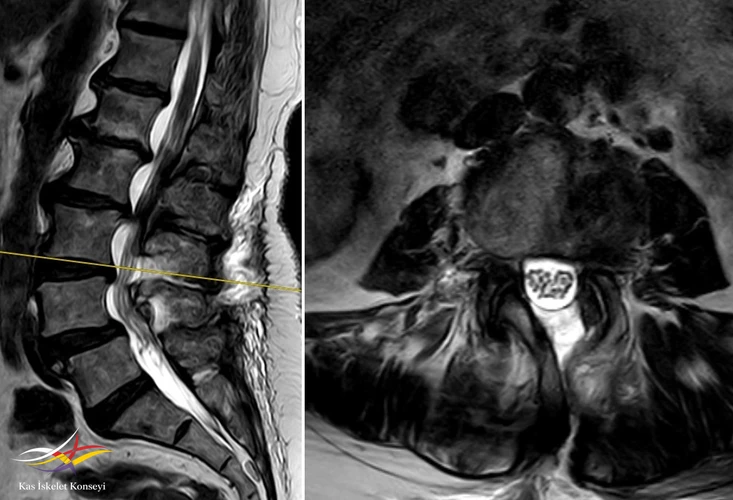

Resim 4. L3-4 seviyesinde belirgin bir kanal darlığı mevcut.

Resim 7. Ameliyat sonrası MRG: L3-4 seviyesindeki dekompresyon görülmekte.